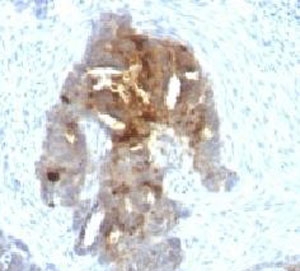

IHC testing of human ovarian carcinoma with TAG-72 antibody (clone TAGP-4).

This antibody recognizes an oncofetal antigen of 220kDa, identified as a tumor-associated glycoprotein (TAG-72) with properties of a mucin. TAG-72 is usually expressed by adenocarcinomas, but is negative in mesotheliomas. Studies have reported that this antibody has 80% sensitivity and 93% specificity for pulmonary adenocarcinoma. Therefore, TAG-72 is a useful marker to distinguish between mesothelioma and adenocarcinoma. However, false positive reactions can occur so results must be interpreted with the utmost caution. This antibody may be useful in the differentiation of non-small cell carcinomas from small cell carcinomas of the lung. The combined use of TAG-72 antibody with a GCDFP-15 antibody is valuable in the diagnosis of apocrine carcinoma.